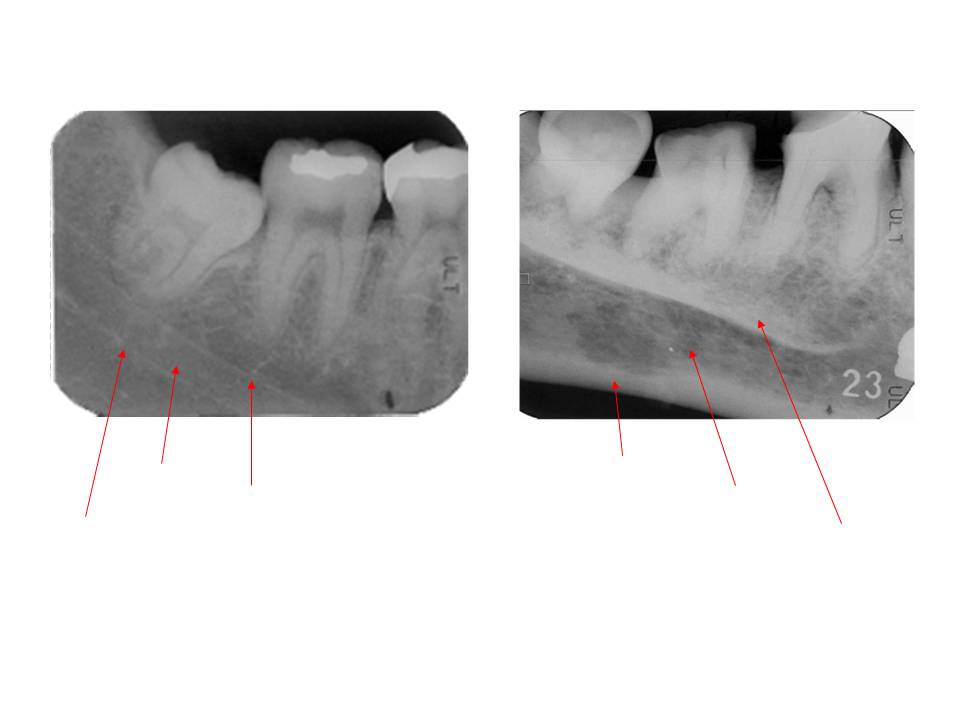

口内法(二等分法・咬合法)撮影の解剖